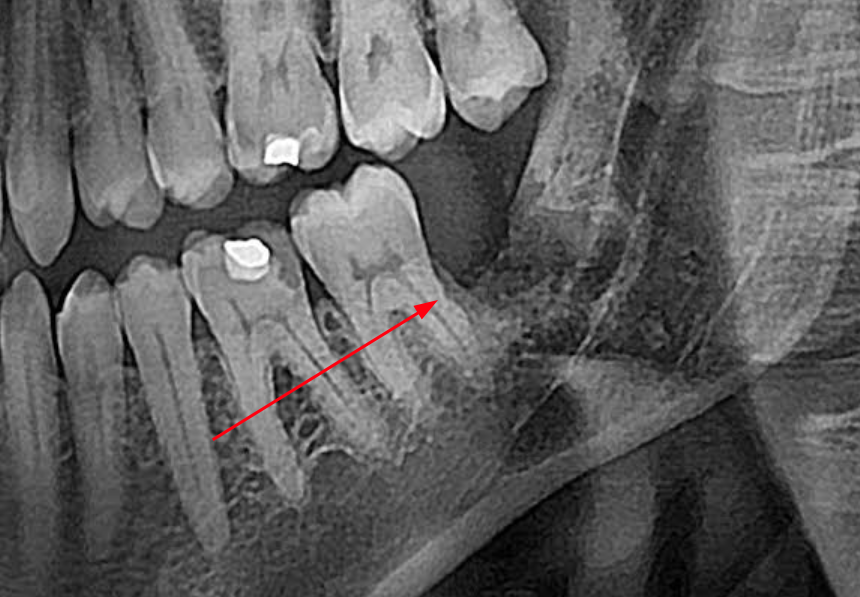

3убастик Опубликовано 27 мая, 2023 Поделиться Опубликовано 27 мая, 2023 Здравствуйте, подскажите как быть. Удалили сложную ретинированную восьмерку снизу, по причине что начала гноиться десна, зуб был в порядке. 10 дней лунка обрабатывалась ванночками из хлоргексидина после еды и еще несколько раз в промежутках. Спустя 10 дней, поняв что лунка не заживает, 10 дней в лунку закладывался левомеколь 3 раза в день на 20 минут на кусочке бинта (сам себе назначил по советам из интернета), убедившись что ничего не меняется на 23 день после удаления пошел к врачу, где был обнаружен небольшой альвеолит. Лунка была промыта хлоргексидином, врач вымыл остаток кровяного сгустка, назначил асепту, которая закладывалась в лунку по 2-3 раза в день. Через 3 дня был повторный осмотр с промыванием лунки, она оказалась чистой, продолжил закладывать асепту (14 дней), лунка особо не заживает до сих пор (сегодня 38 дней после операции и 15 дней как закладываю асепту), сделал повторный снимок, сходил еще раз на осмотр, врач сказал что стало немного получше, кюретаж не требуется, предложил продолжить до месяца использовать асепту и ждать пока затянется. В последние пару дней пару раз после закладывания асепты щипало в лунке минут по 10-15, до этого не было такого. Другой хирург посоветовал закладывать солкосерил, но меня смущает что через это лекарство может передаться болезнь Крейтцфельда-Якоба, которая аукнуться может через 5-15 лет и закончиться очень плачевно, плюс сам солкосерил сейчас стоит космических денег - за 5 г. тубу около 5 тысяч рублей. Подскажите, стоит ли использовать солкосерил, или может есть какие-то безопасные препараты для ускорения эпителизации? Прикладываю снимки до и после, плюс фото самой лунки, может кто на снимках что увидит почему не затягивается. И еще вопрос, на 7 зубе это что за вмятинка, отметил стрелкой на фото? Не может быть повреждения во время операции? Сверлили много... До удаления: После удаления: Лунка: Ссылка на комментарий

Irouil Опубликовано 27 мая, 2023 Поделиться Опубликовано 27 мая, 2023 Здравствуйте! Я предпочитаю не использовать адгезивные пасты в заживающих лунках удалённых зубов. В большинстве случаев достаточно антисептического эффекта Метрогила Дента 1-2 раза в день в лунку (на 10-15 минут и потом обязательно выполоскать/вымыть) и промывание лунки точечно (из шприца) Хлоргексидином 0,05% 2-3 раза в день Но Вы уже достаточно неуспешно позанимались самолечением, я бы не советовал повторять подобный опыт. Чтобы ответственно Вам что-то рекомендовать нужен очный осмотр P.S. не вижу ни одного признака травмы соседнего зуба в результате удаления, со стороны лунки удалённого зуба осталась нетронутая костная стенка, которая пострадала бы первой 1 Ссылка на комментарий